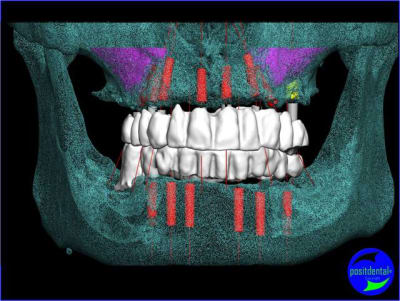

projet implantaire pour février

1er étape le wax-Up, dans ce cas clinique il est réalisé en 3D